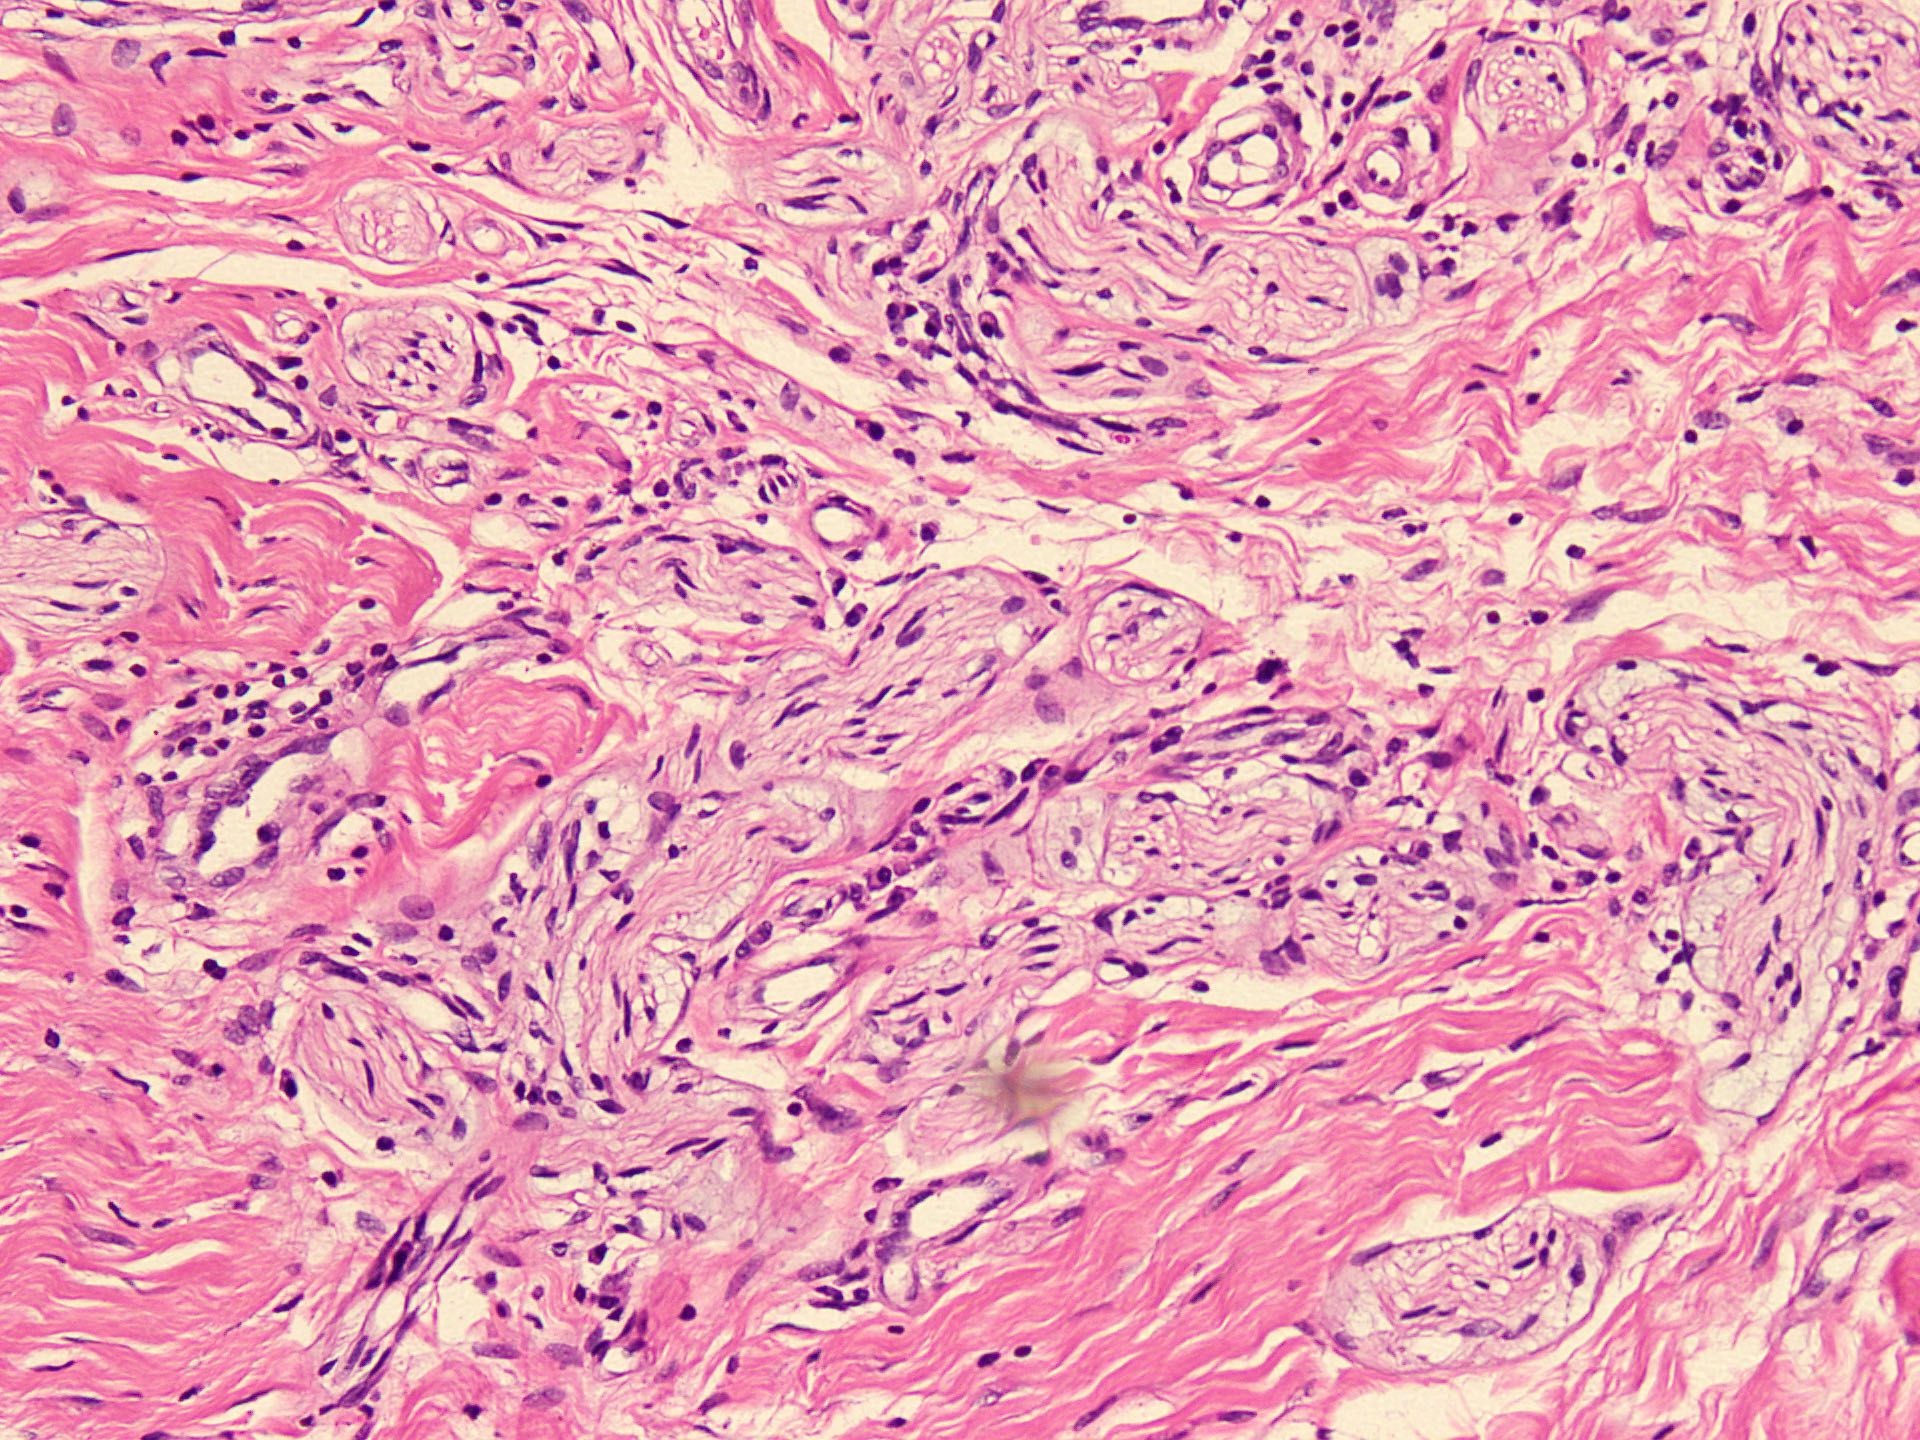

Microscopic (histologic) description

- Circumscribed, unencapsulated spindle cell proliferation arranged in short bundles comprised of axons, Schwann cells, endoneurial cells and perineurial cells (World J Clin Cases 2020;8:3821, Acta Biomed 2020;91:122, StatPearls: Neuroma [Accessed 21 September 2022])

- Peripheral palisading is not present (World J Clin Cases 2020;8:3821)

- Prominent scar tissue with dense collagen may be present (Acta Biomed 2020;91:122, StatPearls: Neuroma [Accessed 21 September 2022])

- Dystrophic calcifications are rarely present (Acta Biomed 2020;91:122)

Microscopic (histologic) images

- Microscopy: The sections examined show a circumscribed, unencapsulated lesion composed of variable sized, closely packed nerve bundle along with scar tissue in the background.

A patient presented with a painful nodule that developed after an amputation of the left first finger. On examination, the nodule is painful. Excision of the lesion is performed which shows the histology above. Which of the following is the most likely diagnosis?